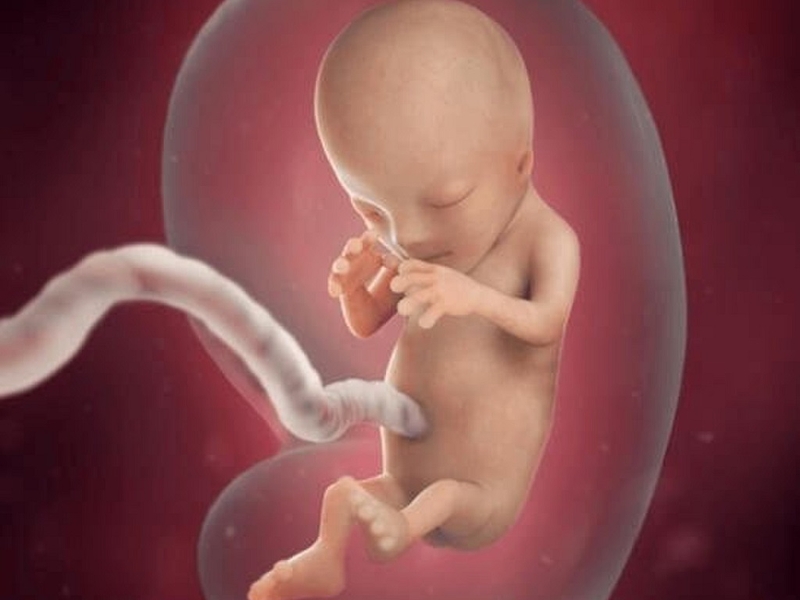

Trong giai đoạn này, thai nhi có kích thước tương đương với một quả quýt, cân nặng khoảng 15g. Cùng lúc này, các cơ quan quan trọng trong cơ thể thai nhi cũng dần được hình thành và ngày càng hoàn thiện hơn trong giai đoạn này.

Như vậy, chiều dài đầu mông thai 12 tuần bao nhiêu là bình thường? Chiều dài đầu mông khi thai ở tuần thứ 12 thường sẽ dao động trong khoảng từ 55 - 65mm, tương đương với thai từ 12 tuần 0 ngày tới 12 tuần 6 ngày. Đặc điểm đáng chú ý nhất trong giai đoạn này là thai nhi đã bắt đầu hình thành một số phản xạ như co duỗi các ngón tay, ngón chân, miệng có phản xạ mút.

Đặc biệt, đây cũng là giai đoạn mà não bộ của trẻ đang phát triển rất mạnh mẽ, cụ thể là các tế bào và các khớp thần kinh. Ngoài ra, hệ xương khớp và các thành phần khác của cơ thể cũng đang phát triển hoàn thiện dần dần. Các nghiên cứu chỉ ra rằng, nhịp tim của thai nhi lúc 12 tuần tuổi nhanh gấp 2 - 3 lần nhịp tim thai của mẹ bầu.